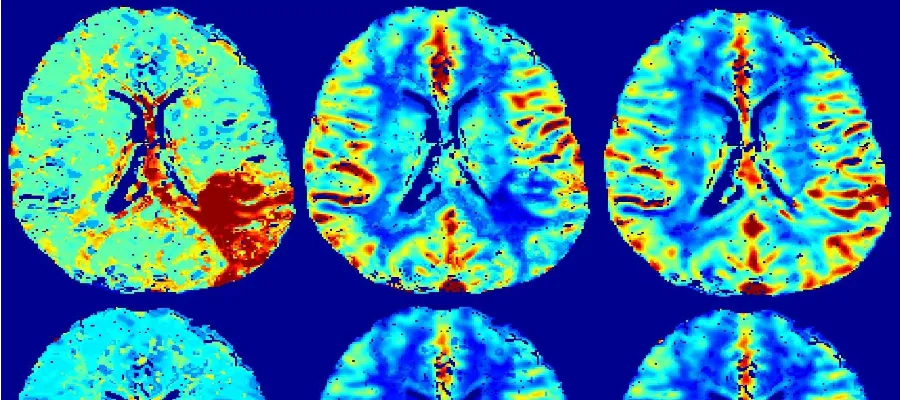

The Brain Research Imaging Centre (BRIC)

Dementia research

Edinburgh is at the forefront of developing advanced imaging techniques to provide insight into the vascular contributions to disease such as dementia.

Stroke research

A £1.2m UK wide collaborative project is being led by Professor Joanna Wardlaw aiming to improve how doctors identify and treat dementia that occurs following a stroke.  The clinical study will involve 2000 stroke patients and Edinburgh is one of nine UK institutions involved.

The new facilities are also at the centre of several recent grants to study small vessel disease.